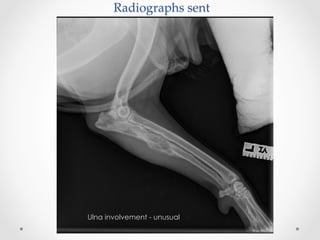

Radiographs  sent

Ulna involvement - unusual

Radiographs  sent No pulmonarymetastatic nodules were seen on chest radiographs